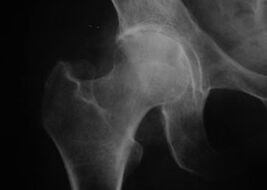

Koksatroza, artroza zgloba kuka

Uz ovu bolest opaža se klasična klinička slika artroze.

Prvi simptom koksartroze je nelagoda u zglobu kuka nakon tjelesne aktivnosti.

S progresivnom koksartrozom povećava se bol, javlja se ukočenost i ograničena pokretljivost.

Bolesnici s težim oblikom koksartroze štede zahvaćeni ekstremitet, izbjegavaju gaziti, au mirovanju biraju položaje u kojima se najmanje osjeća bol.